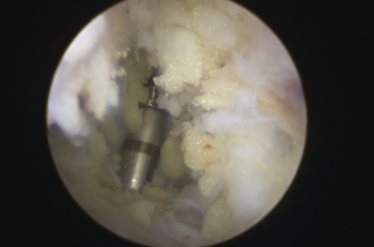

手术入路——两个0.5厘米小孔

镜下刨削刺激病变的距骨软骨

镜下打入锚钉固定距腓前韧带

术中,探查见关节腔大量增生病变滑膜组织,距骨软骨面多处软骨剥脱变性,明显的外侧副韧带损伤后继发关节炎表现。手术医生在踝关节镜下刨削刺激病变的距骨软骨,打入锚钉固定距腓前韧带,圆满完成手术。